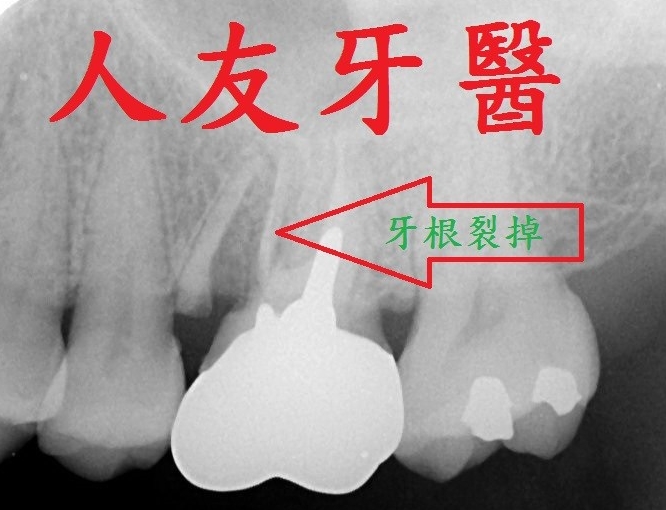

植體周圍炎牙齒從外表看不出來,需從x光片才能看出來,為避免造成植體周圍組織發炎,甚至破壞到周遭骨頭,平時應注重牙齒清潔保養,選擇刷毛軟的牙刷清潔 , 搭配牙間刷去清潔牙縫 , 並定期回診檢查,確保牙齒健康。